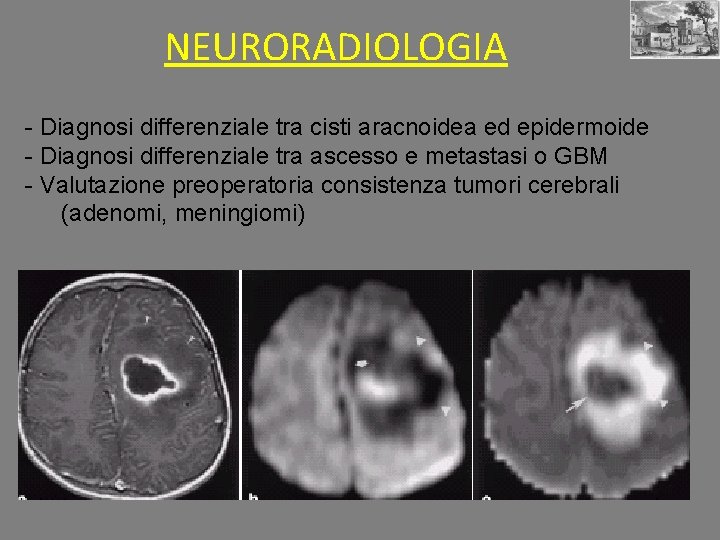

NEURORADIOLOGIA - Diagnosi differenziale tra cisti aracnoidea ed epidermoide - Diagnosi differenziale tra ascesso e metastasi o GBM - Valutazione preoperatoria consistenza tumori cerebrali (adenomi, meningiomi)